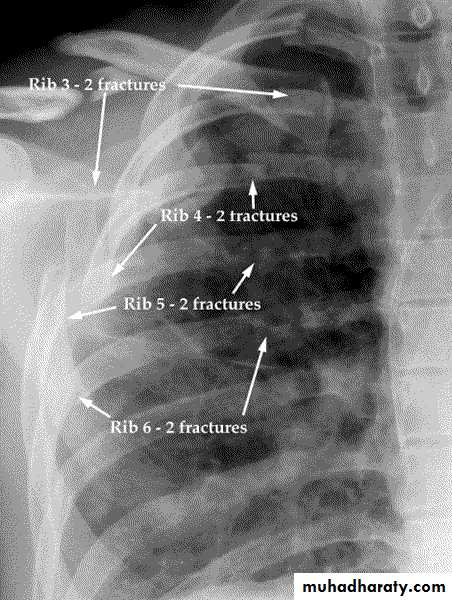

Rib fractures

Most common thoracic injuryMost commonly 5th to 9th ribs

Poor protection

Localised pain, tenderness, crepitus

CXR to exclude other injuries

Analgesia..avoid taping

Upper ribs, clavicle or scapula fracture: suspect vascular injury

Fractures of 8th to 12th ribs can damage underlying abdominal solid organs:

Liver

Spleen

Kidneys